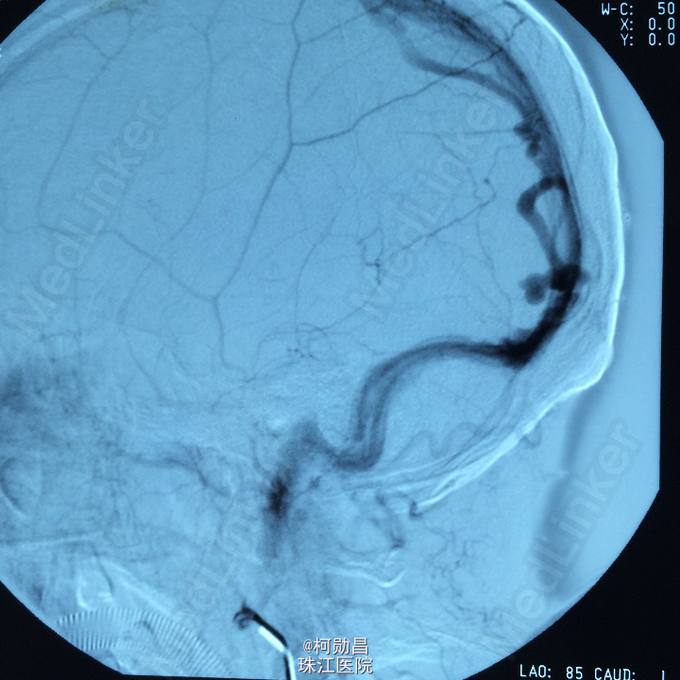

查体:神经系统检查无明显阳性体征。 全脑DSA提示为左枕硬脑膜动静脉瘘

诊断:左枕硬脑膜动静脉瘘 处理:行DSA明确诊断,并予血管内栓塞治疗

术后患者症状明显缓解,随访半年,仍有轻微头痛反复发作,可能与栓塞材料神经压迫作用所致,服用药物止痛。 本病治疗方案决定于临床表现和血管造影发现。轻微局部症状的患者可采取保守治疗。血管内栓塞为目前首选治疗方法,主要选择经静脉途径,其治愈率远高于经动脉途径[5]。可供选择的栓塞材料有弹簧圈、液胶、可脱落球囊、Onyx液体栓塞剂。血管内栓塞失败或无栓塞指征者,可考虑手术治疗。对于瘘口细小复杂者,放疗也有一定疗效术后并发症来自于静脉窦内血栓形成或栓塞材料对周围结构的压迫作用。部分栓塞成功的患者在随访过程中仍有再次复发可能,其原因包括弹簧圈的位置移动,暂时闭塞的瘘口的再通,血流动力学变化和新瘘的产生等。